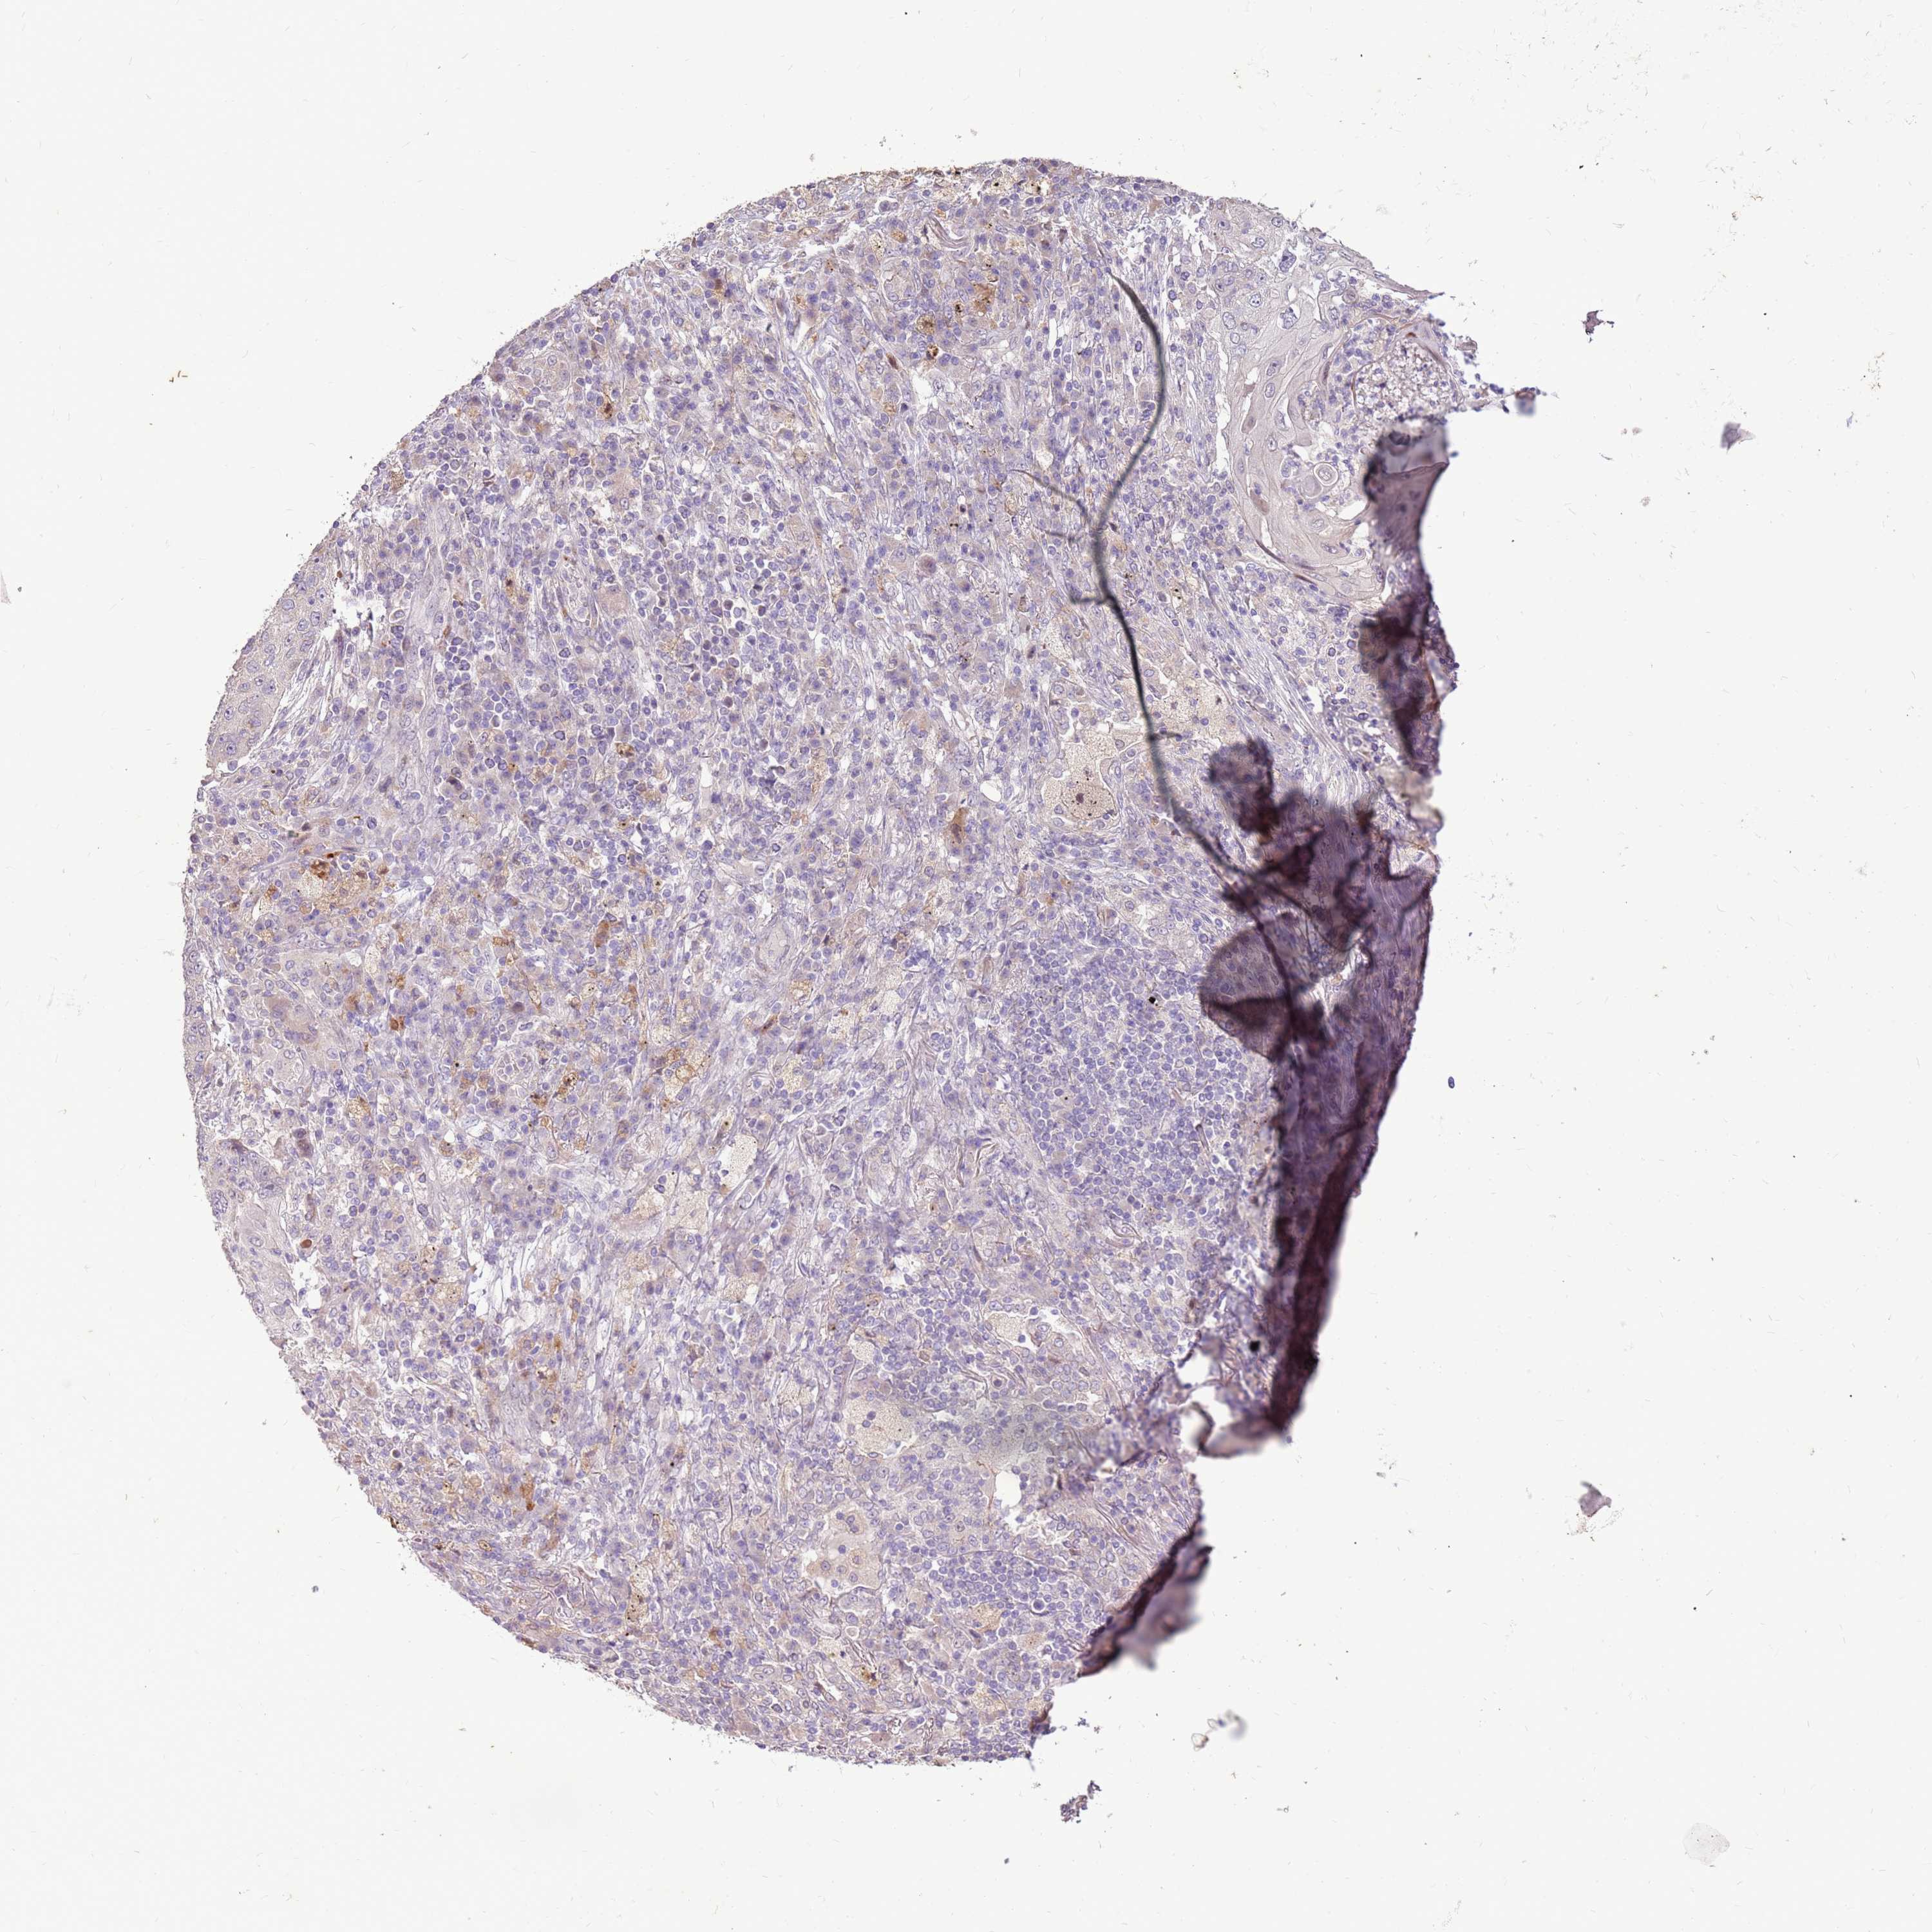

LUNG SQUAMOUS CELL CARCINOMA (TCGA) - Interactive survival scatter ploti

The Survival Scatter plot shows the clinical status (i.e. dead or alive) for all individuals in the patient cohort, based on the same data that underlies the corresponding Kaplan-Meier plots. Patients that are alive at last time for follow-up are shown in blue and patients who have died during the study are shown in red.

The x-axis shows the expression levels (FPKM) of the investigated gene in the tumor tissue at the time of diagnosis. The y-axis shows the follow-up time after diagnosis (years). Both axes are complimented with kernel density curves demonstrating the data density over the axes. The top density plot shows the expression levels (FPKM) distribution among dead (red) and alive patients (blue). The right density plot shows the data density of the survived years of dead patients with high and low expression levels respectively, stratified using the cutoff indicated by the vertical dashed line through the Survival Scatter plot. This cutoff is automatically defined based on the FPKM cutoff that minimizes the p-score. The cutoff can be changed by dragging the vertical line or by entering a cutoff value in the square labeled "Current cut-off".

Under the Survival Scatter plot the p-score landscape (black curve; left axis) is shown together with dead median separation (red curve; right axis). Dead median separation is the difference in median mRNA expression between patients who have died with high and low expression, respectively. It is calculated as follows: median FPKM expression of dead patients with high expression - median FPKM expression of dead patients with low expression. This is intended to aid the user in visually exploring custom cutoffs and the associated p-scores and dead median separation.

Individual patient data is displayed and can be filtered by clicking on one or more of the category buttons on the top of the page. Categories describing expression level and patient information include: high, low, alive, dead, female, male and tumor stages. The scale of the x-axis can be toggled between linear and log-scale by clicking on the "x log" button. Mouse-over function shows TCGA ID, patient information and mRNA expression (FPKM) for each patient.

& Survival analysisi

Kaplan-Meier plots summarize results from analysis of correlation between mRNA expression level and patient survival. Patients were divided based on level of expression into one of the two groups "low" (under cut off) or "high" (over cut off). X-axis shows time for survival (years) and y-axis shows the probability of survival, where 1.0 corresponds to 100 percent.

LGI4 is not prognostic in Lung Squamous Cell Carcinoma (TCGA)